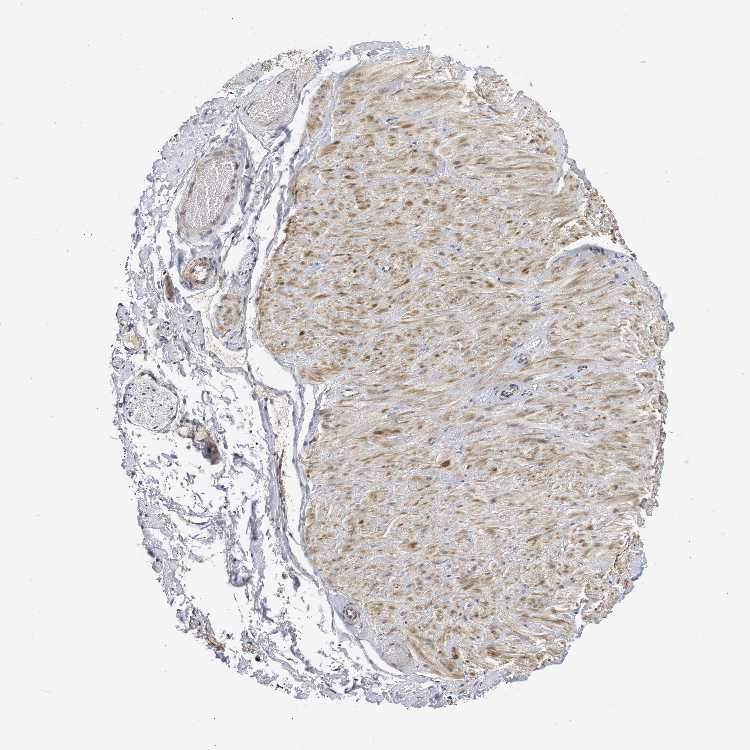

ADIPOSE TISSUE - Antibody stainingi

Antibody staining in the annotated cell types in the current human tissue is reported as not detected, low, medium, or high, based on conventional immunohistochemistry profiling in selected tissues. This score is based on the combination of the staining intensity and fraction of stained cells.

Each image is clickable and will lead to virtual microscopy that enables deeper exploration of all samples and also displays staining intensity scores, fraction scores and subcellular localization as well as patient and tissue information for each sample.

Antibody HPA018483Antibody HPA019081Antibody HPA021152

Adipocytes Not detectedNot detectedMedium